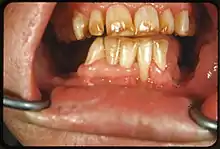

It appears as a range of visual changes in enamel[4] causing degrees of intrinsic tooth discoloration, and, in some cases, physical damage to the teeth. The severity of the condition is dependent on the dose, duration, and age of the individual during the exposure.[1] The "very mild" (and most common) form of fluorosis, is characterized by small, opaque, "paper white" areas scattered irregularly over the tooth, covering less than 25% of the tooth surface. In the "mild" form of the disease, these mottled patches can involve up to half of the surface area of the teeth. When fluorosis is moderate, all of the surfaces of the teeth are mottled and teeth may be ground down and brown stains frequently "disfigure" the teeth. Severe fluorosis is characterized by brown discoloration and discrete or confluent pitting; brown stains are widespread and teeth often present a corroded-looking appearance.[1]

The adequate diagnosis of fluorosis can be diagnosed by visual clinical examination. This requires inspection of dry and clean tooth surfaces under a good lighting.[6] There are individual variations in clinical fluorosis manifestation which are highly dependent on the duration, timing, and dosage of fluoride exposure.There are different classifications to diagnose the severity based on the appearances. The clinical manifestation of mild dental fluorosis is mostly characterised a snow flaking appearance that lack a clear border, opaque, white spots, narrow white lines following the perikymata or patches as the opacities may coalesce with an intact, hard and smooth enamel surface on most of the teeth.[7] With increasing severity, the subsurface enamel, all along the tooth becomes more porous. Enamel may appear yellow/ brown discolouration and/ or many and pitted white-brown lesions that look like cavities. They are often described as "mottled teeth".[8] Fluorosis does not cause discolouration to the enamel directly, as upon eruption into the mouth, affected permanent teeth are not discoloured yet. In dental enamel, fluorosis causes subsurface porosity or hypomineralizations, which extend toward the dentinal-enamel junction as the condition progresses and the affected teeth become more susceptible to staining. Due to diffusion of exogenous ions (e.g., iron and copper), stains develop into the increasingly and abnormally porous enamel.[7]

| Severe | 5 | All enamel surfaces are affected and hypoplasia is so marked that the general form of the tooth may be affected. The major diagnostic sign of this classification is discrete or confluent pitting. Brown stains are widespread and teeth often present a corroded-like appearance. |